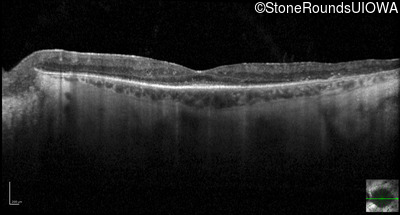

Optical Coherence Tomography - Right - 20/40 +2

Exemplar / OCT Stack

OCT Stack